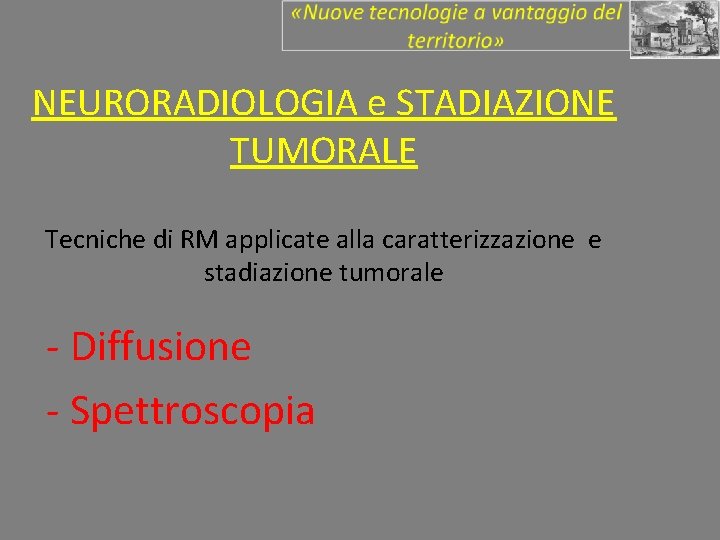

NEURORADIOLOGIA e STADIAZIONE TUMORALE Tecniche di RM applicate alla caratterizzazione e stadiazione tumorale - Diffusione - Spettroscopia